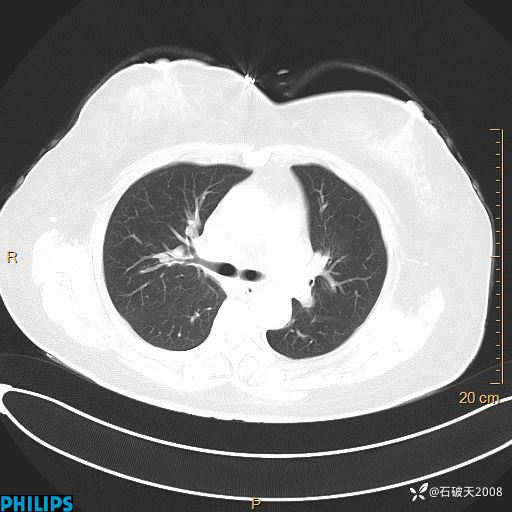

肺结节病?纵膈型肺癌?淋巴瘤?有点意思,欢迎围观

女 52岁 主 诉:咳嗽10余天,咳痰2天。

现病史:10余天前无明显诱因出现咳嗽,呈阵发性干咳,伴咽喉部发痒,无咽痛,无咳痰,无鼻塞、流涕、打喷嚏,无发热、畏寒、寒颤,无头痛、头晕,无胸闷、胸痛,无反酸、烧心,无腹痛、腹泻,无尿频、尿急,无皮疹等,在当地诊所求治,给予口服药物治疗(具体不详),病情无好转。遂在当地社区卫生服务中心开具口服药物治疗(具体不详),疗效欠佳。2天前出现咳痰,在我院门诊求治,行胸部CT提示肺部感染,建议住院,患者要求口服药物治疗,目前仍咳嗽、咳白色粘痰,白天量多,夜间自觉喉部喘鸣音,遂再次来院就诊,以“肺部感染”为诊断收入院。发病以来,神志清,精神可,饮食可,夜间睡眠差,大小便正常,近期体重无明显变化。

肺窗